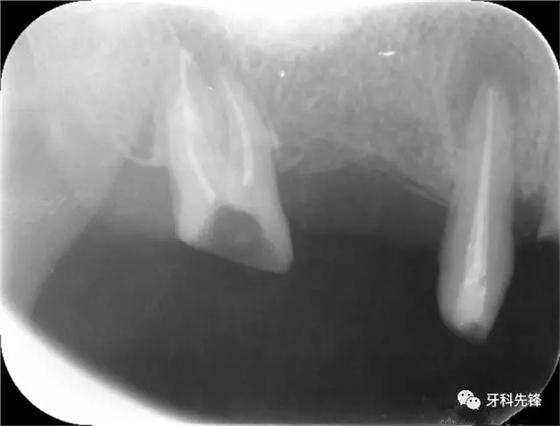

圖1術(shù)前X光片

640.webp.jpg

圖8治療術(shù)后X光片

640.webp (10).jpg